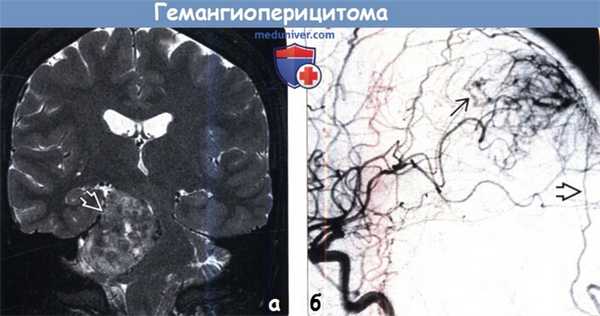

(а) МРТ, Т2-ВИ, режим подавления сигнала от жира, корональный срез: определяется крупное гетерогенное объемное образование, сконцентрированное в правом мостомозжечковом углу и имеющее связь с твердой мозговой оболочкой. При резекции была диагностирована гемангиоперицитома.

(б) ЦСА, контрастирование ВСА, боковая проекция: определяется артериовенозное шунтирование с ранним венозным дренированием. Также наблюдается дополнительный питающий сосуд — ветвь затылочной артерии. Для гемангиоперицитом характерно смешанное кровоснабжение из сосудов твердой и мягкой мозговых оболочек. Часто полезно проведение предоперационной эмболизации.

(а) МРТ, Т2-ВИ, режим подавления сигнала от жира, корональный срез: в нижних отделах лобной доли определяются гетерогенное гиперинтенсивное объемное образование с участками потери сигнала за счет эффекта потока в его центральной части, а также эрозия кости, что является характерными признаками гемангиоперицитомы.

(б) МРТ, постконтрастное Т1-ВИ, режим подавления сигнала от жира, корональный срез: у того же пациента определяется диффузный характер контрастирования дольчатого объемного образования. Картина при визуализации имитирует менингиому. КТ может быть полезна для более точного определения эрозии кости. В круг дифференциального диагноза при диагностической визуализации также должны быть включены метастатическое поражение твердой мозговой оболочки и лимфома.